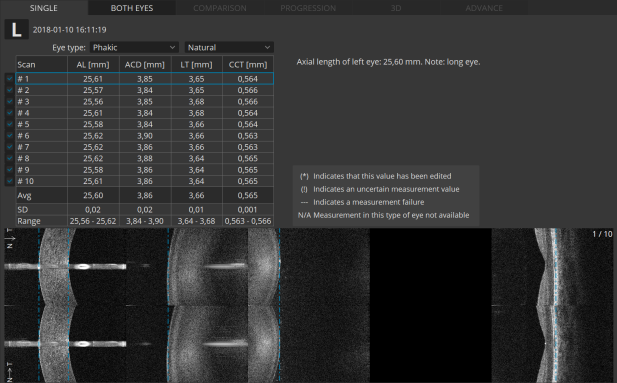

Опциональные модули: Ангиография, биометрия, кератотопография